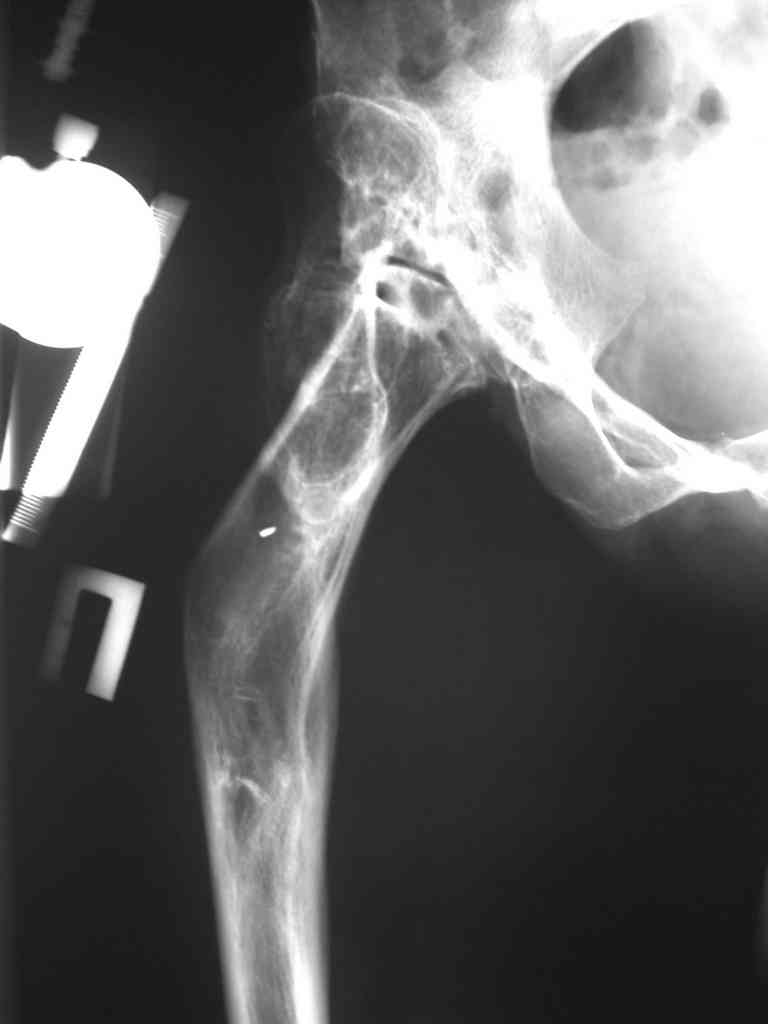

Поднят очень интересный вопрос об эффективности создания опорного бедра по Илизарову у молодых пациентов (ок). Наверное мне не повезло и я не

видел положительных результатов после этих операций, а вот проблемных больных приходится видеть достаточно часто. Причем сроки их обращения

после остеотомии короткие - 3-5 лет, а выполнение эндопротезирования после остеотомии на двух уровнях с многоплоскостной деформацией является

серьезным испытанием и для пациента и для хирурга. Я тоже не сторонник эндопротезирования в молодом возрасте, но уж после неудачных остеотомий

остеотомии. Я представил Р-граммы больных с неудачными р-ми после остеотомий.

Эндопротезирование у них было на порядок сложнее в отличие от артропластики без проведения остеотомии.